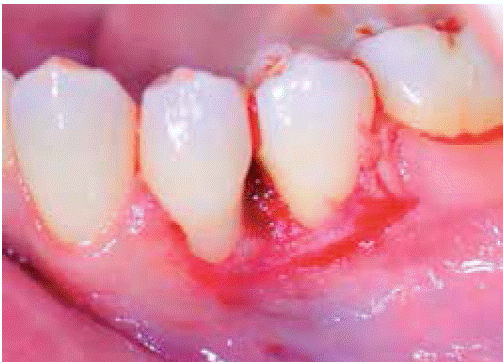

Clinical examination revealed an inflammatory gingival lesion at the level of teeth 3.4 and 3.5. Measuring approximately 15x9 mm. The lesion covered the vestibular side of the clinical crown, it was firm, lobulated, of rugged texture and bleeding upon stimulus (Figures 1and2). Periodontal assessment did not reveal periodontal pockets; presence of plaque was observed, and an O'Leary oral hygiene index of 18.75 was determined. Radiographic evaluation revealed absence of interproximal contact between teeth 3.4 and 3.5 as well as restorative material in the interproximal area (Figure 3).

An excisional biopsy of the lesion was taken during the second session (Figure 4). The lesion was removed during this intervention as well as a healthy tissue margin and adjacent periosteum. For histopathological examination, a sample was taken, and transported in 10% formaldehyde. After this, soft tissue was re-contoured (gingivoplasty) (Figure 5), and a periodontal cement pack was placed. Use of analgesic for 48 hours was prescribed, as well as 0.12% Chlorhexidine rinses. Due to allergic reactions these rinses had to be discontinued after five days due to onset of ulcerative lesions at the level of attached gingiva.